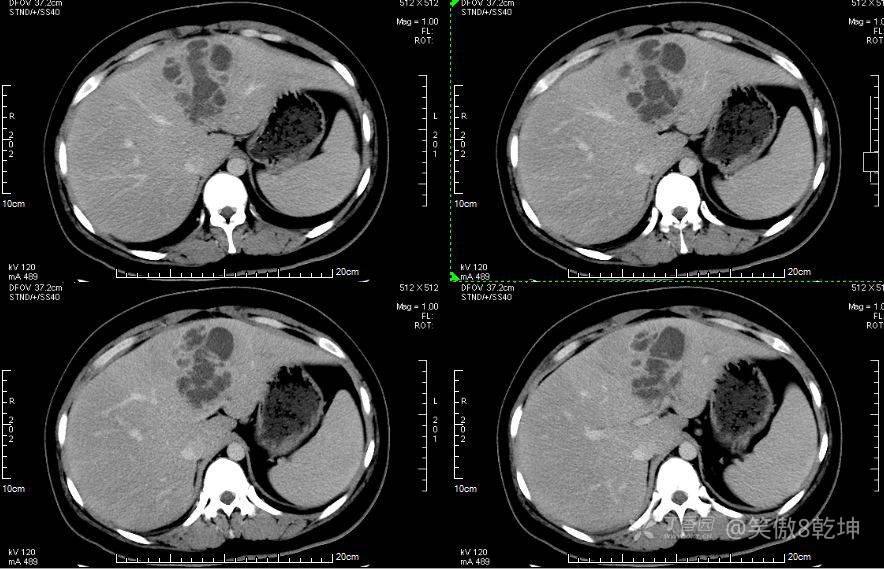

诊断似乎倾向于肝脓肿了,与患者或家属沟通后完善上腹部强化CT:

证实为肝脓肿,至此,诊断思路似乎清晰起来,患者血糖的升高使得微小血管容易出现循环障碍,同时白细胞的吞噬能力及抗感染能力下降,所有易出现感染性疾病。而肝脓肿通常不容易早期发现。患者的年龄同时让临床医生不容易想到此诊断。